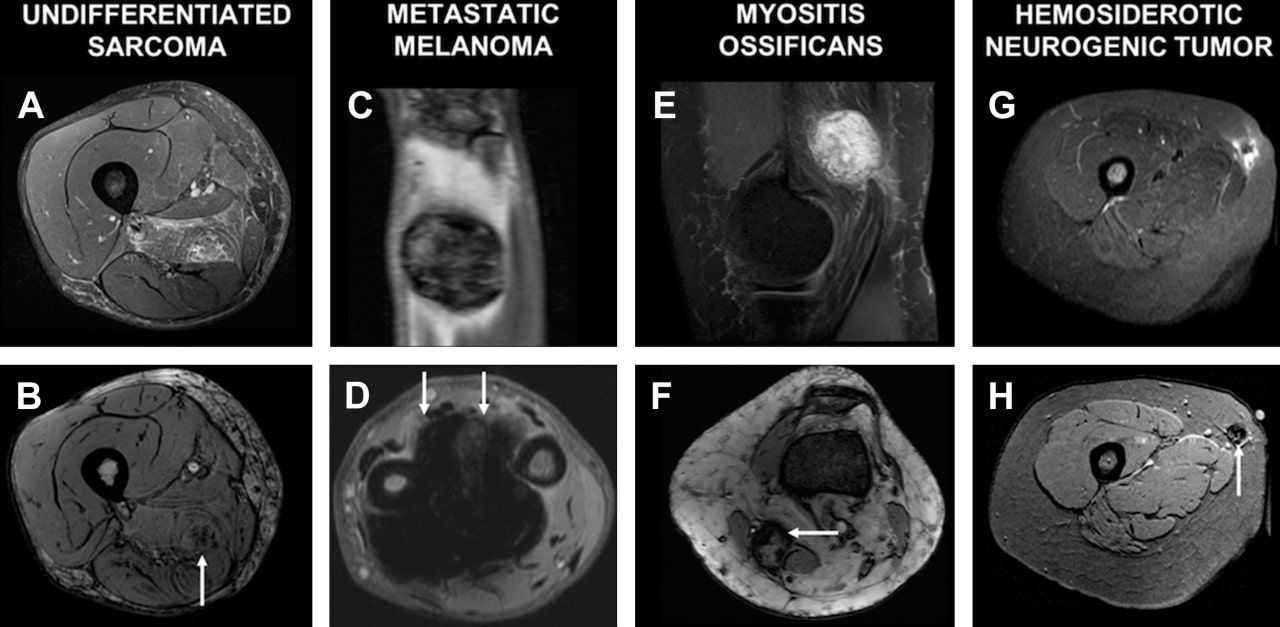

Преимущества МРТ мягких тканей включают ее высокую чувствительность к различным патологиям. Метод позволяет выявлять опухоли, травмы, воспалительные процессы и другие изменения на ранних стадиях. Таким образом, своевременное обращение за этим видом диагностики может существенно улучшить прогнозы лечения.

- Подозрения на опухоли. При наличии новообразований или кист необходимо уточнить их природу и распространенность с помощью МРТ.